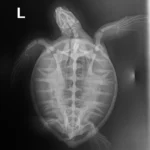

2.05 kg juvenile Atlantic Green sea turtle

Patient Injuries

External Carapace Notes: Notch on left marginal neat tip

Plastron: Minor abrasions

External Wounds: Small wound on right front flipper Lightly bleeding